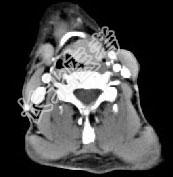

- 单项选择题男,53岁, 咽部不适半年余,近两个月感咽部疼痛, 声嘶,CT如图所示, 应诊断是 ( )

D、喉癌

E、梨状窝癌